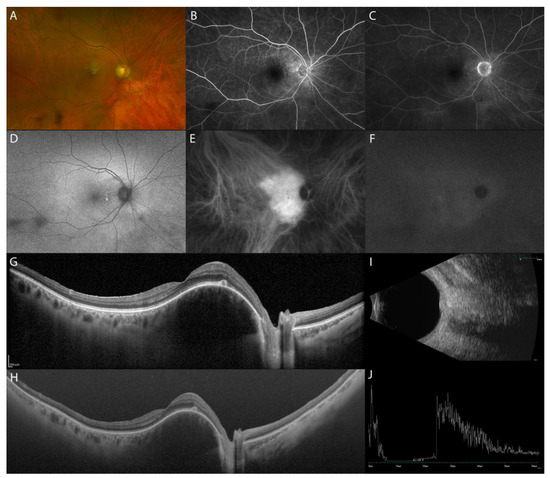

Sakata et al. reported a unique finding in VKH patients in the non-acute uveitic stage, “choroidal bulging”, which seems to be related to active posterior segment inflammation. It is characterized by a localized thickening of the choroid, which assumes a convex appearance with consequent bulging of the RPE/Bruch’s membrane reflective complex anterior (Figure 2) [14].

MMI of the chronic recurrent uveitic phase of VKH disease. UWF fundus image (A). FA (B,C). FAF (D). ICGA with multiple coalescent hypofluorescent dots (E,F). EDI-OCT showing corresponding localized thickening of the choroid, which assumes a convex appearance with consequent bulging of the outer retina (‘choroidal bulging’), indicated by the asterisk (G) and reduction post-treatment (H).

During the convalescent stage in patients with long-standing VKH disease, the choroid thickness turned out to be progressively thinner on EDI-OCT than that of normal individuals [15].